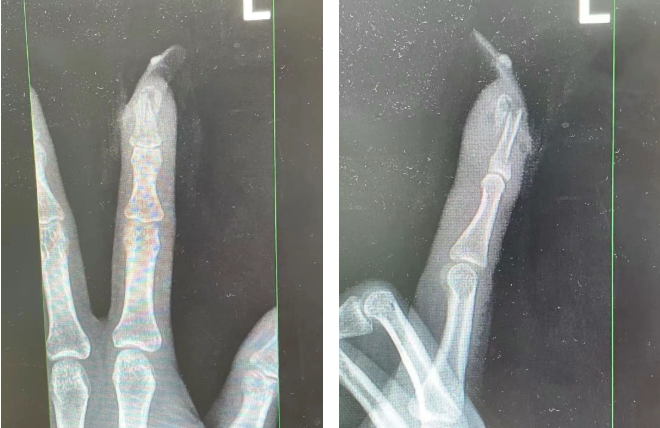

image.png

王女士受傷手指的X光影像。圖源:杭州市臨平區(qū)中西醫(yī)結(jié)合醫(yī)院